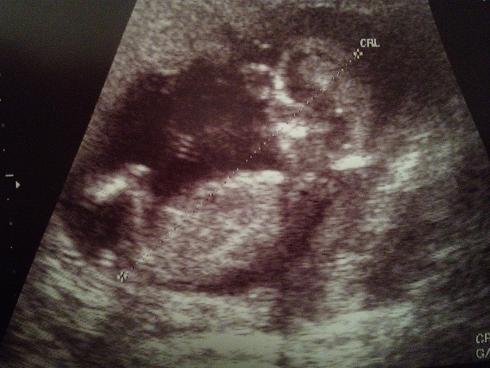

Attachment 11205 Attachment 11206 Attachment 11207

AAA I think girl!!!! Beautiful baby!!!!!!!

Looks like a little girl - congrats crystalclear!

Does look girly :)

Maybe pink.

I think girl x